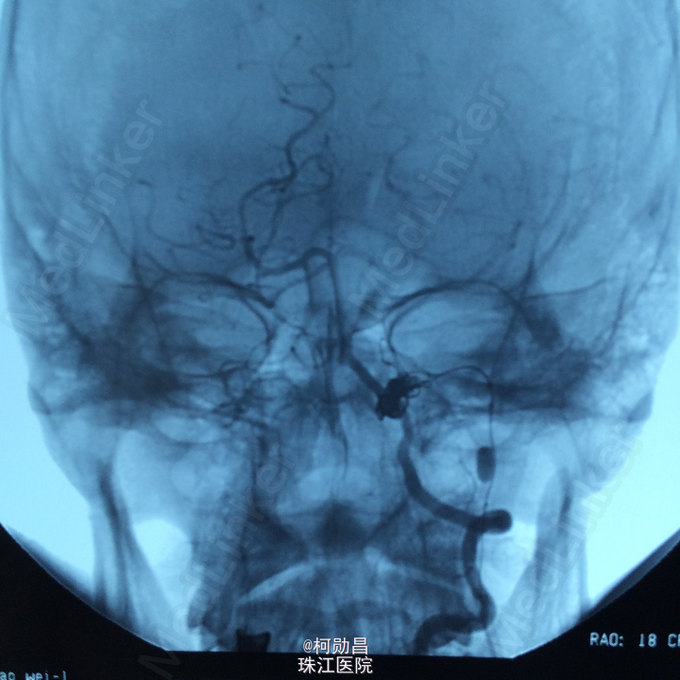

诊断:颈内动脉假性动脉瘤破裂 处理:急诊行DSA检查,提示颈内动脉海绵窦段动脉瘤形成并破裂向鼻腔引流,予血管内栓塞治疗,将动脉瘤腔堵塞,患者出血停止。